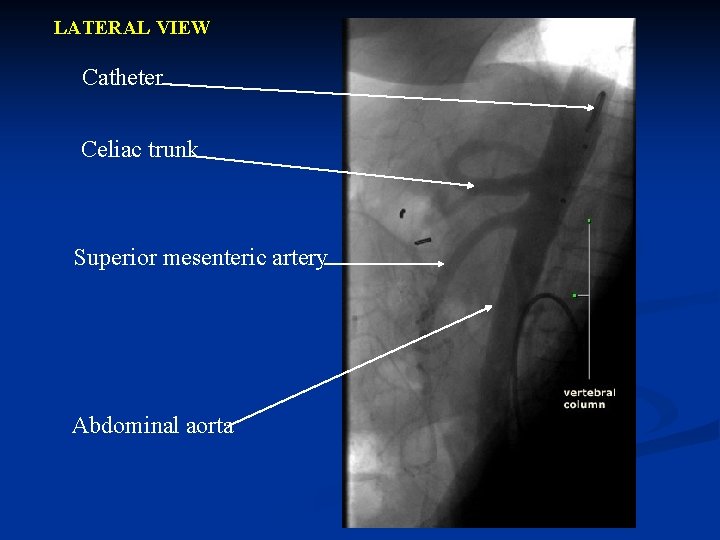

LATERAL VIEW Catheter Celiac trunk Superior mesenteric artery Abdominal aorta